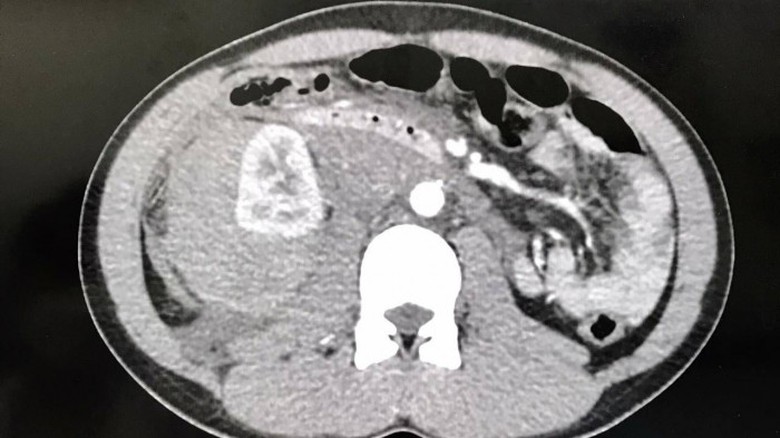

Ảnh chụp CT Scanner trước khi can thiệp nội mạch.

Qua thăm khám và thực hiện các cận lâm sàng cần thiết, các bác sĩ chẩn đoán người bệnh bị chấn thương thận phải độ IV (AAST) gây xuất huyết nội và vỡ gan hạ phân thùy VII độ I. Người bệnh được tiến hành cấp cứu, điều trị nội khoa tích cực, theo dõi sát mạch, huyết áp và tình trạng bụng.